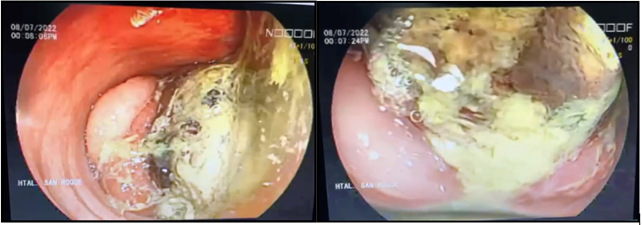

Videocolonoscopia: se explora hasta topografía de colon izquierdo con buena preparación, donde se observa invaginación intestinal, a expensas de lesión vegetante, por segmentos necrosada, ulcerada y friable al tacto endoscópico que ocupa el 100% de la luz, no permitiendo el paso del mismo, se realizan maniobras de desinvaginación, las cuales no son efectivas.

La colonoscopia permite identificar la intususcepción y su ubicación, pudiendo tomar biopsia en el caso de que se presente una lesión orgánica primaria. Sin embargo, se debe tener precaución con la biopsia colonoscópica, debido al riesgo de perforación resultante de isquemia tisular crónica y el compromiso vascular10.